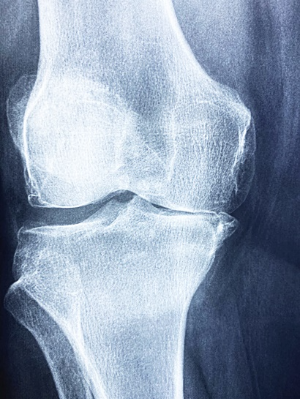

3. 관절 부음

류마티스 관절염은 주로 양쪽의 대칭적인 작은 관절을 표적으로 합니다. 손가락, 발가락의 관절, 손목, 발목, 팔꿈치, 무릎 등이 부어오르고 아프며 따끔거립니다. 이런 부음은 염증으로 인해 관절 주변의 활막이 팽창하고 관절액이 증가하기 때문입니다.